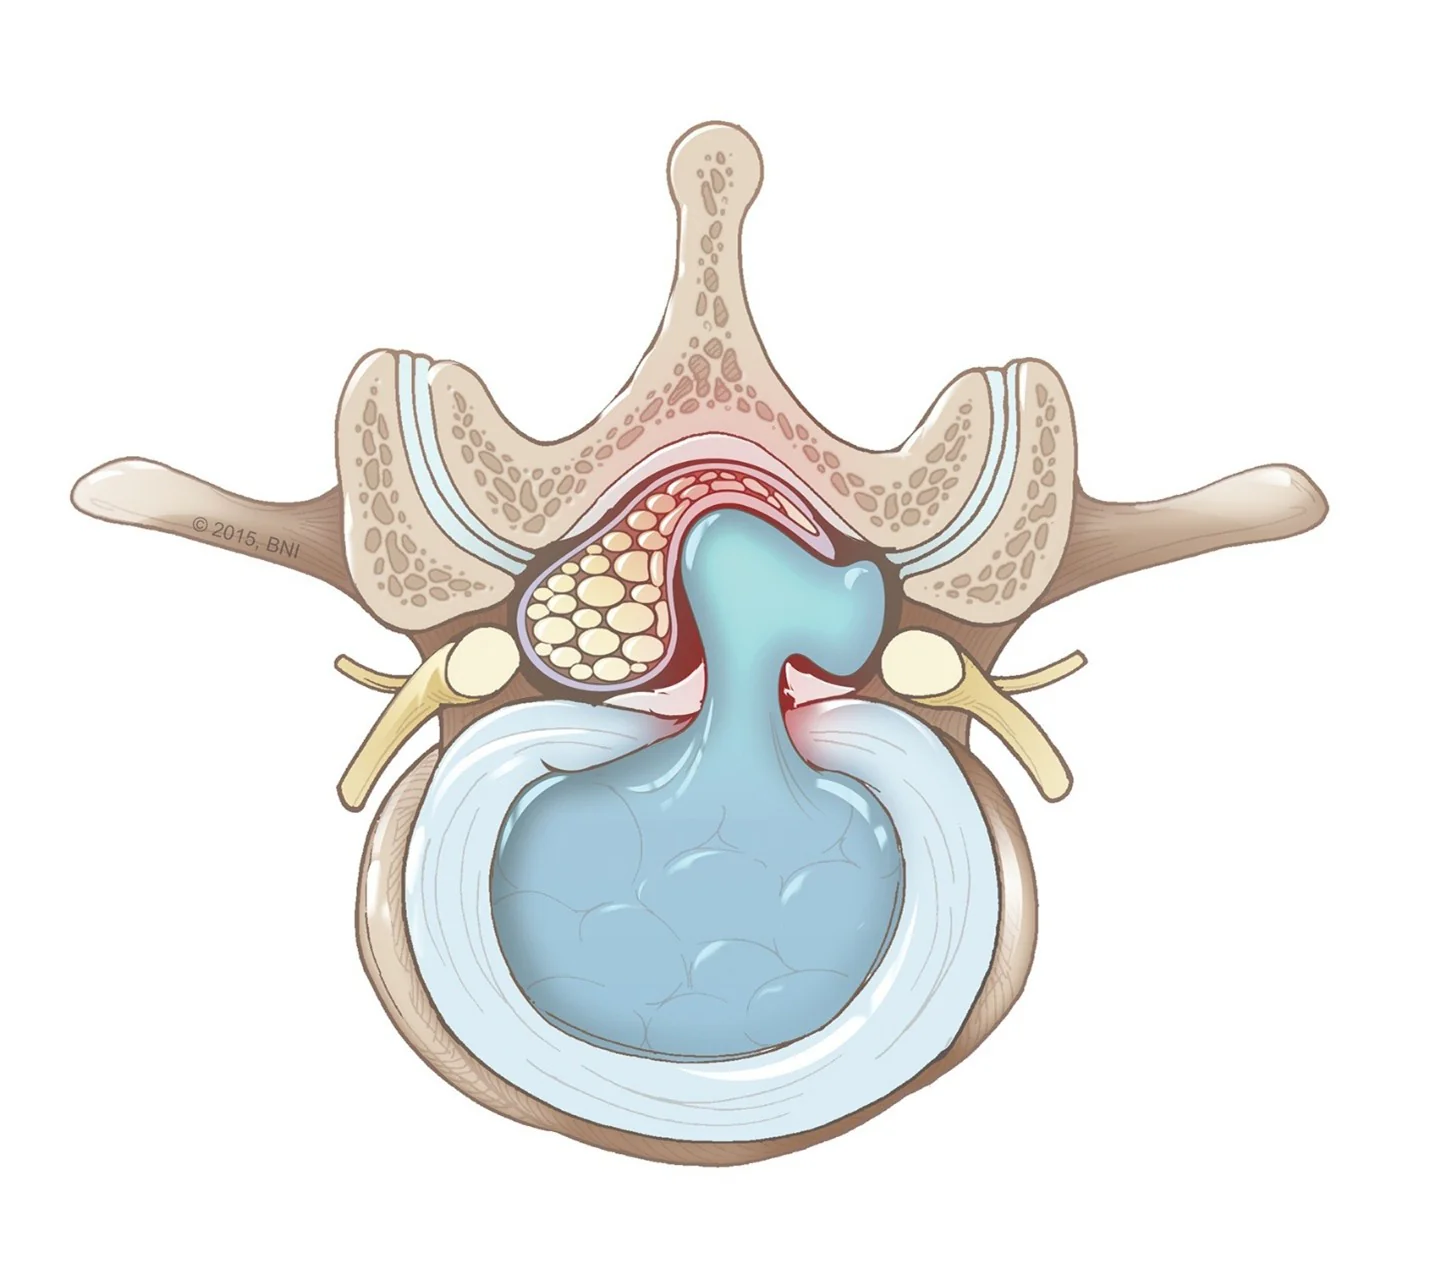

A avaliação da força e alteração de sensibilidade com o sinal de Lasègue são considerados chave para o diagnóstico. Em hérnias muito volumosas ou associadas a estenoses do canal vertebral, pode existir compressão conjunta das raízes lombares, determinando uma síndrome da cauda equina: quadro clínico grave com hipotonia muscular, arreflexia, diminuição severa da movimentação dos membros inferiores e, eventualmente, disfunções esfincterianas. Nesses casos, o tratamento mais escolhido é a cirurgia descompressiva de urgência.

Síndrome da cauda equina por hérnia de disco lombar volumosa